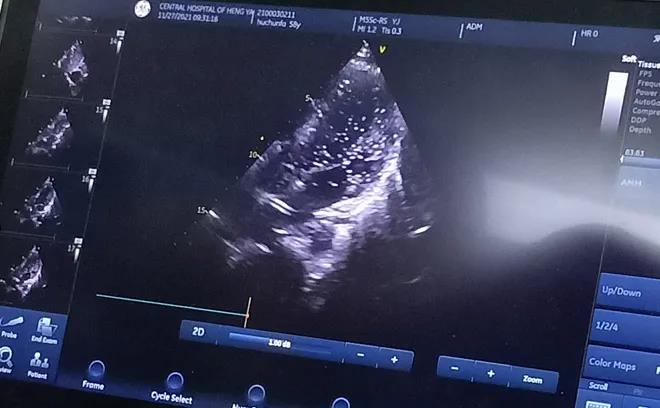

經充分的術前準備后, 11月27日上午,胡先生接受局部麻醉下經皮介入PFO封堵術,手術全程病人清醒,醫(yī)生一邊與胡先生交流,一邊進行手術,術后無傷口創(chuàng)面。患者當天即下床活動,復查心臟彩超提示封堵器位置良好。